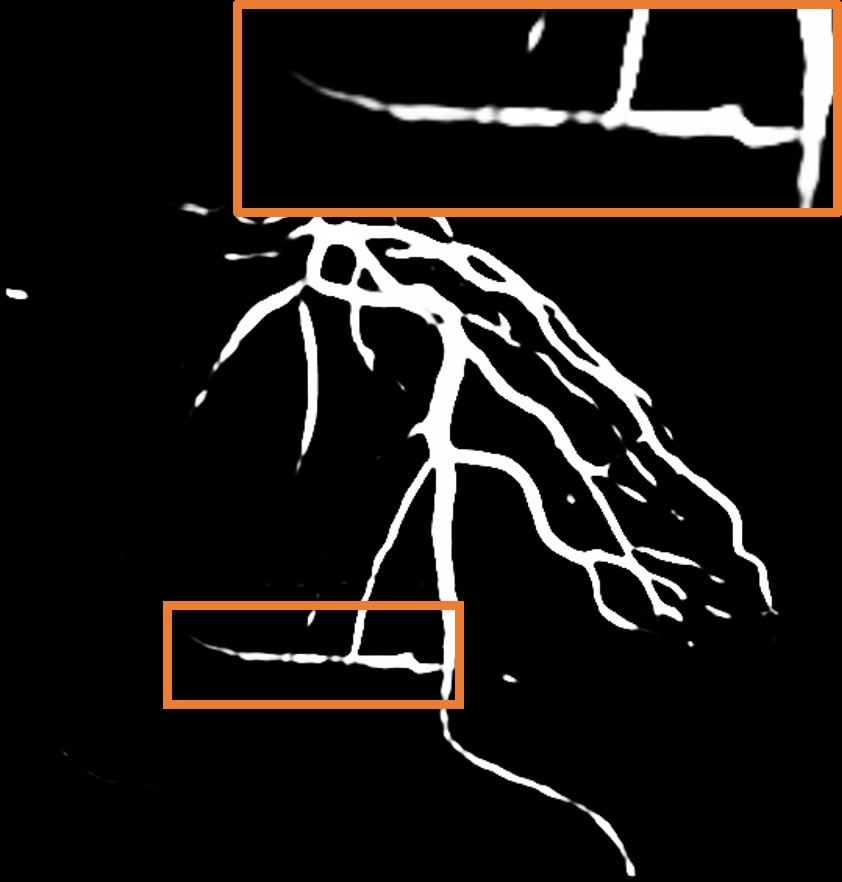

Layer separation bootstrapping.

To validate the effectiveness of the layer separation bootstrapping, we train foreground and background canonical images using the same representation. The results are shown in Table 2, where optimizing both foreground and background canonical images simultaneously leads to a decrease in the Dice score by 0.0055. The comparison is shown in Figure 8 (a), where the orange area indicates the difference between without and with Layer separation bootstrapping. The bottom-right corner shows a zoom-in patch, highlighting the significant effect of the bootstrapping step.

Hessian prior loss .

To test the effect of the Hessian prior loss, we remove the Hessian prior loss. As a result, the segmentation performance, as shown in Table 2, also decreases the Dice score by 0.0063. The comparison between the without and with is shown in Figure 8 (b), where the orange area indicates the difference between them. The zoom-in patch shows that our model predicts less noticeable vascular regions incorporating the Hessian prior loss .

Parallel vessel motion loss .

We conduct an experiment to assess the effect of the parallel vessel motion loss by removing it from the training pipeline. As shown in Table 2, the segmentation performance decreases the Dice score by 0.0047. Without this loss to enforce parallelism between blood and vessels, the segmentation results are negatively affected. In addition, the comparison between without and with is shown in Figure 8 (c). The zoom-in patch shows that the image with has clearer segmented vascular regions.